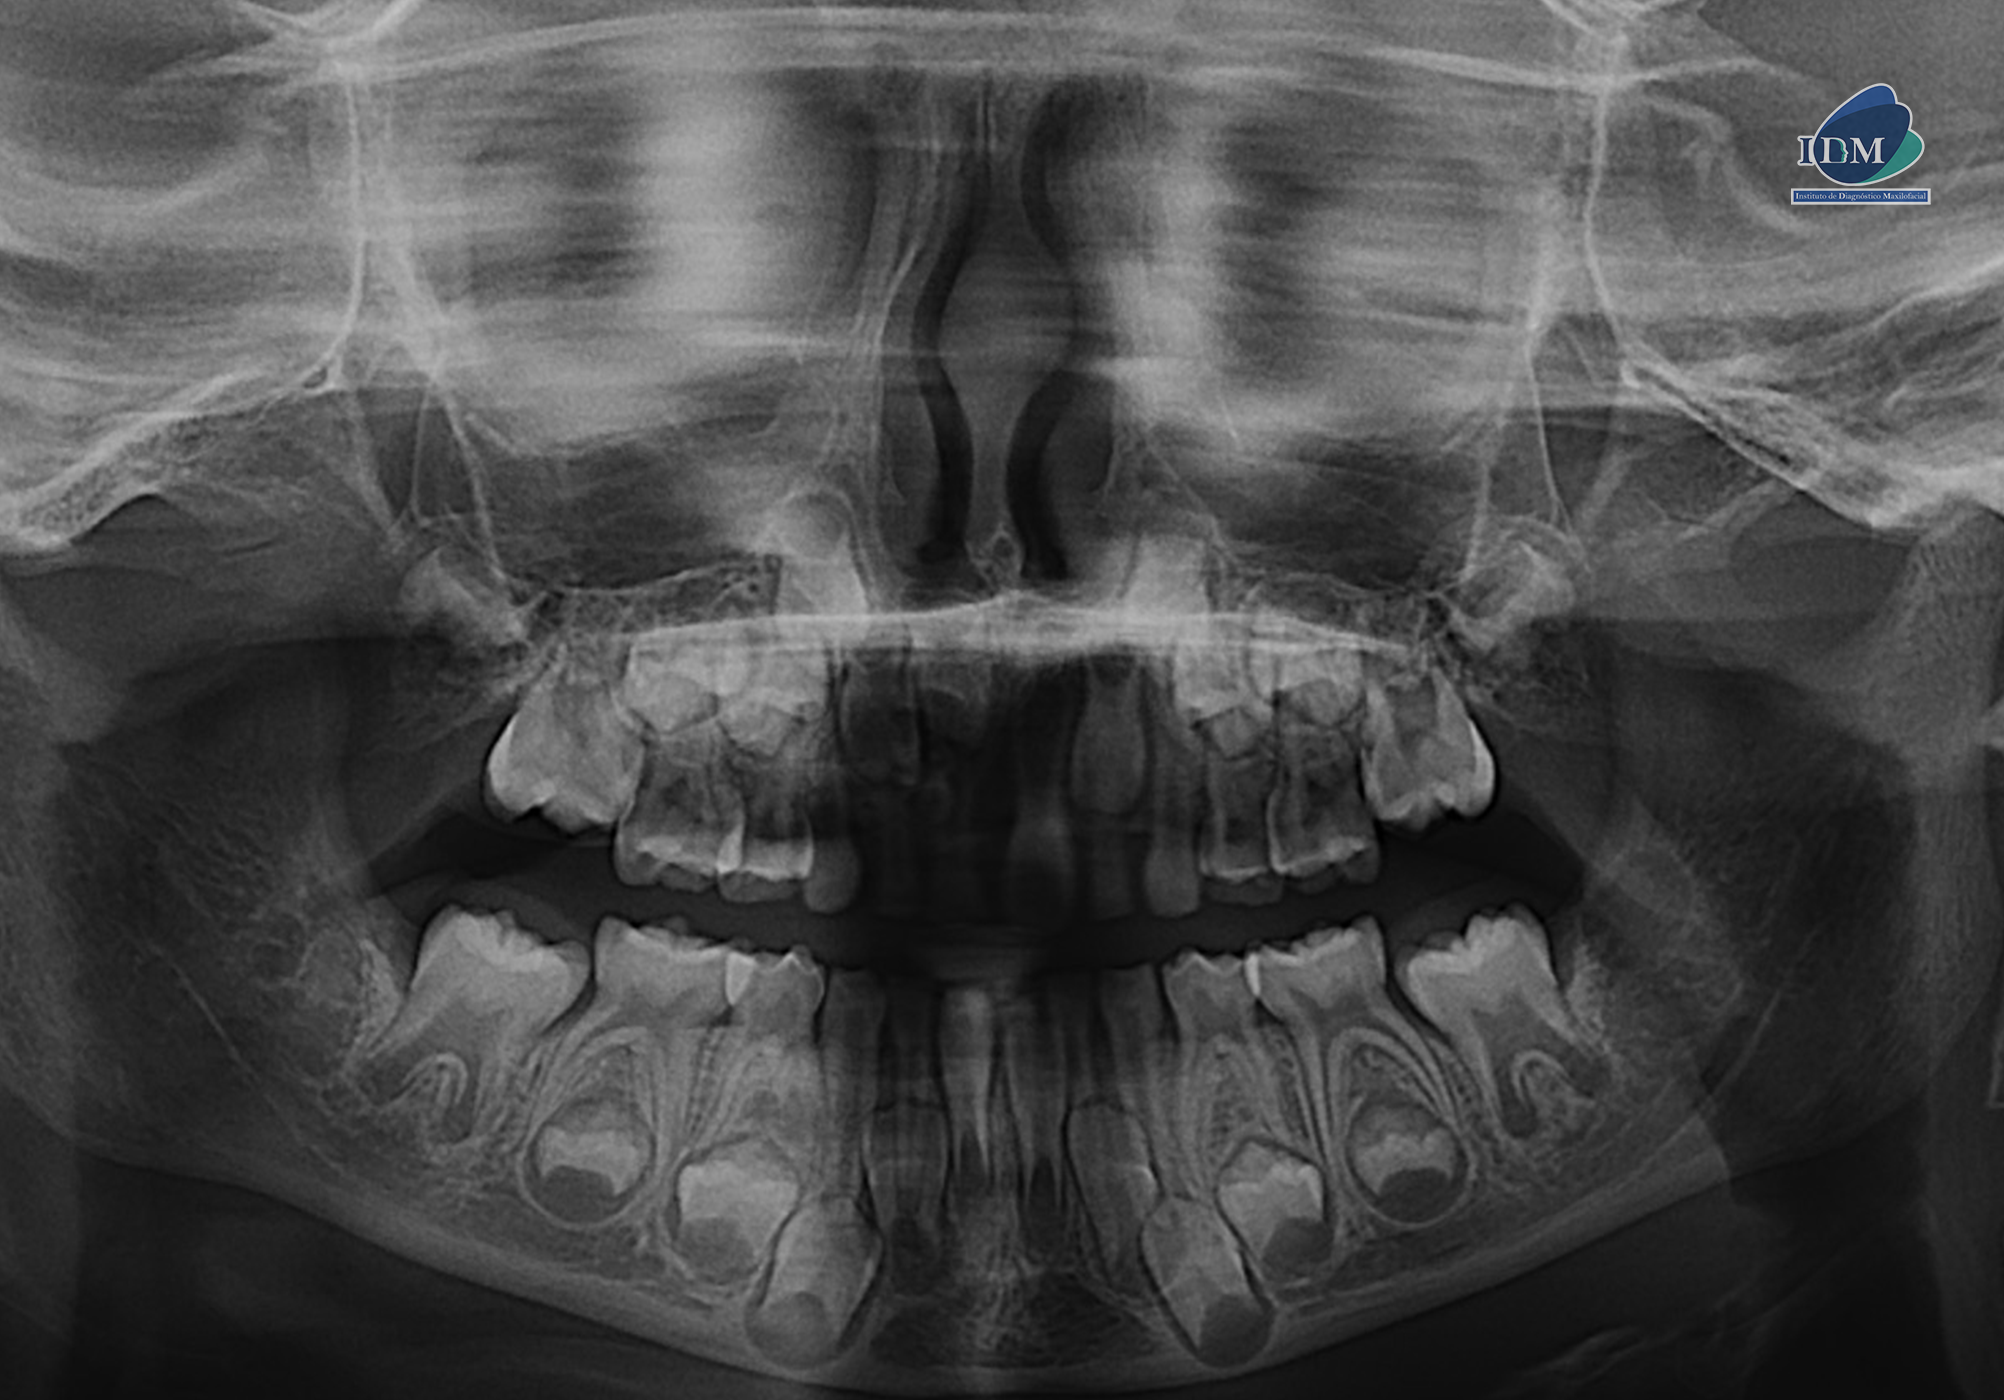

Radiografia Panorámica

En la radiografía panorámica (Figura 1), se aprecia imagen radiopaca de densidad dentaria, de limites definidos circunscrita con un halo radiolúcido, proyectado en tercio medio y apical de pieza 52-51, observándose en el interior múltiples dentículos.

A la evaluación de la tomografía volumétrica (CBCT) en los cortes axiales (Figura 2) y transaxiales(Figura 3), se aprecia múltiples dentículos circunscrito de un halo hipodenso, localizada en palatino del tercio apical y medio de piezas 52-51, que ocasiona el desplazamiento de la pieza 11 hacia cefálico y adelgazamiento de la tabla ósea palatina En las reconstrucciones 3D se representa odontoma compuesto. (Figura 4).